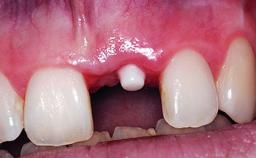

Replacement of an Ankylosed Upper Left Central Incisor: Bone Augmentation and Socket Grafting, Late Placement of an RC Bone Level Implant

A 15-year-old male patient was referred to us by his pediatric dentist in June 2004 for evaluation of treatment options for his failing tooth 21. The patient had recently seen an endodontist for internal bleaching and been advised that there had been significant resorption and ankylosis. The patient’s mother was concerned because the tooth appeared shorter than the adjacent one. His past dental history was significant for trauma (September 2001), where the tooth had been avulsed and reimplanted. Teeth 11 and 21 had been endodontically treated.

Provisional Implant-Supported Prosthesis Prosthodontic margin > 3 mm apical to mucosal margin Prosthodontic margin > 3 mm apical to mucosal margin

Interim Prosthesis during Healing Fixed Fixed